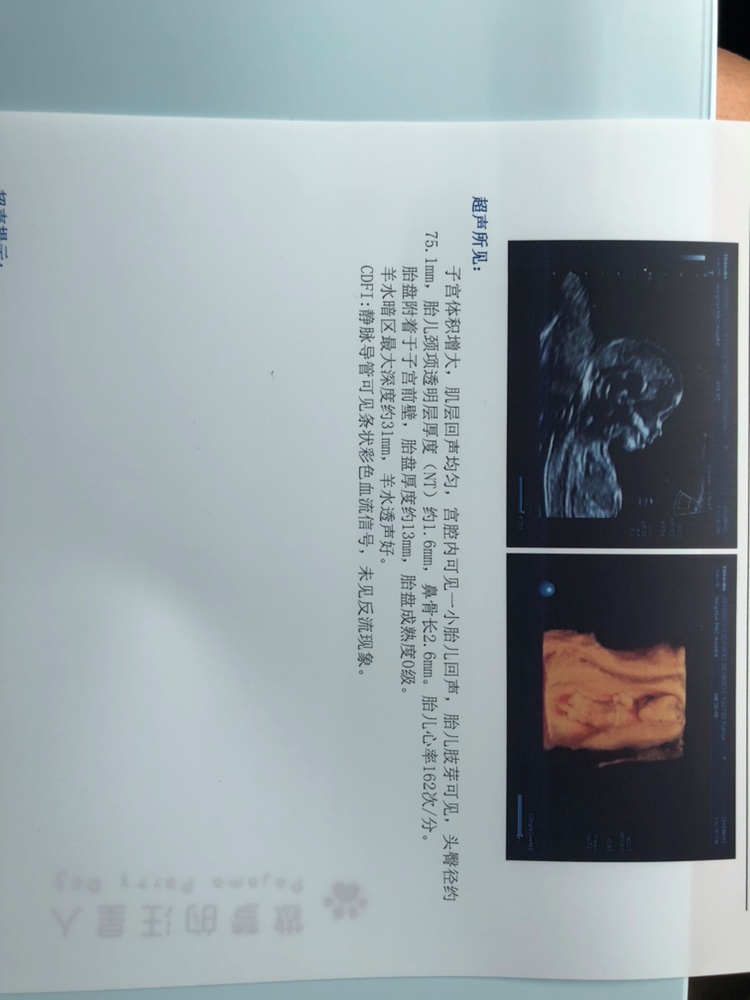

孕28周+0天

看不出来,看心率像女